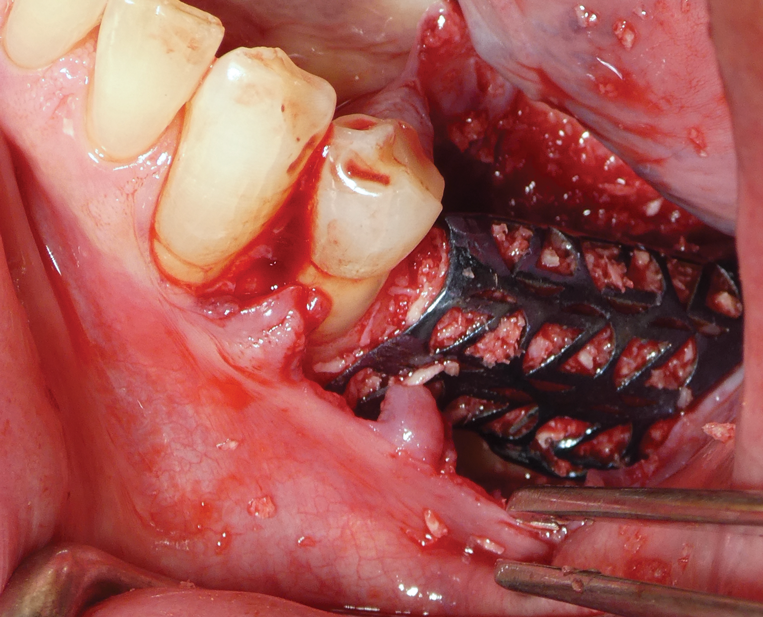

After implant placement, the mesh was secured in place. Special care was taken to ensure that pre-designed fixation holes did not align with anatomical sensitive areas. The mesh was loaded with the grafting material and placed over the implant. It was fixated with two screws (1.2 mm x 6 mm) designed within the mesh, as planned (Figure 4).

Fig 4. Mesh placed on donor site.

Figure 4

Fig 14. Titanium mesh placed intraorally.

Figure 14